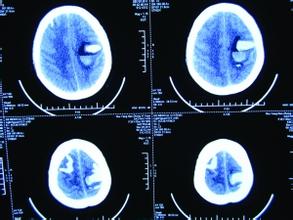

脑出血病人脑CT图